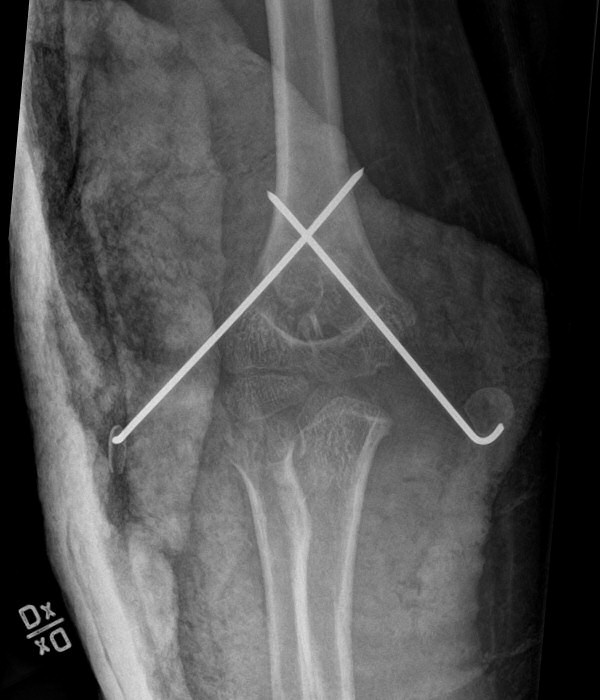

Suprakondylar humerusfraktur, Gartland 3, före och efter operation med stiftning